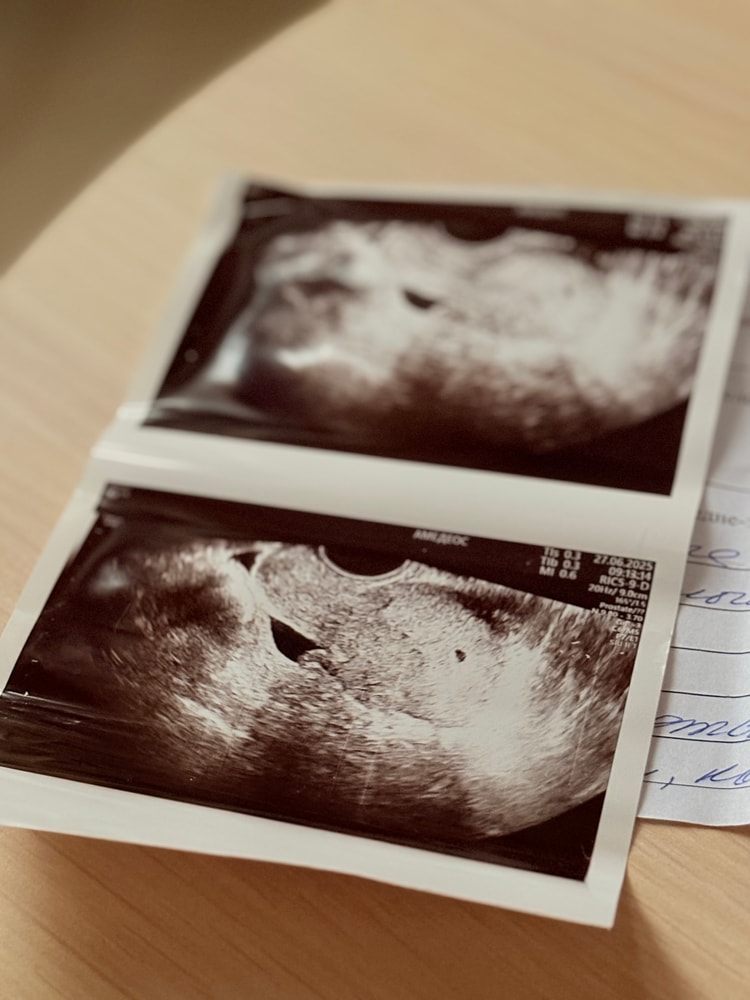

Первый снимок🌸

Нам 4 недели и 5 дней🫶🏼 Желточный мешочек 1.9 мм.